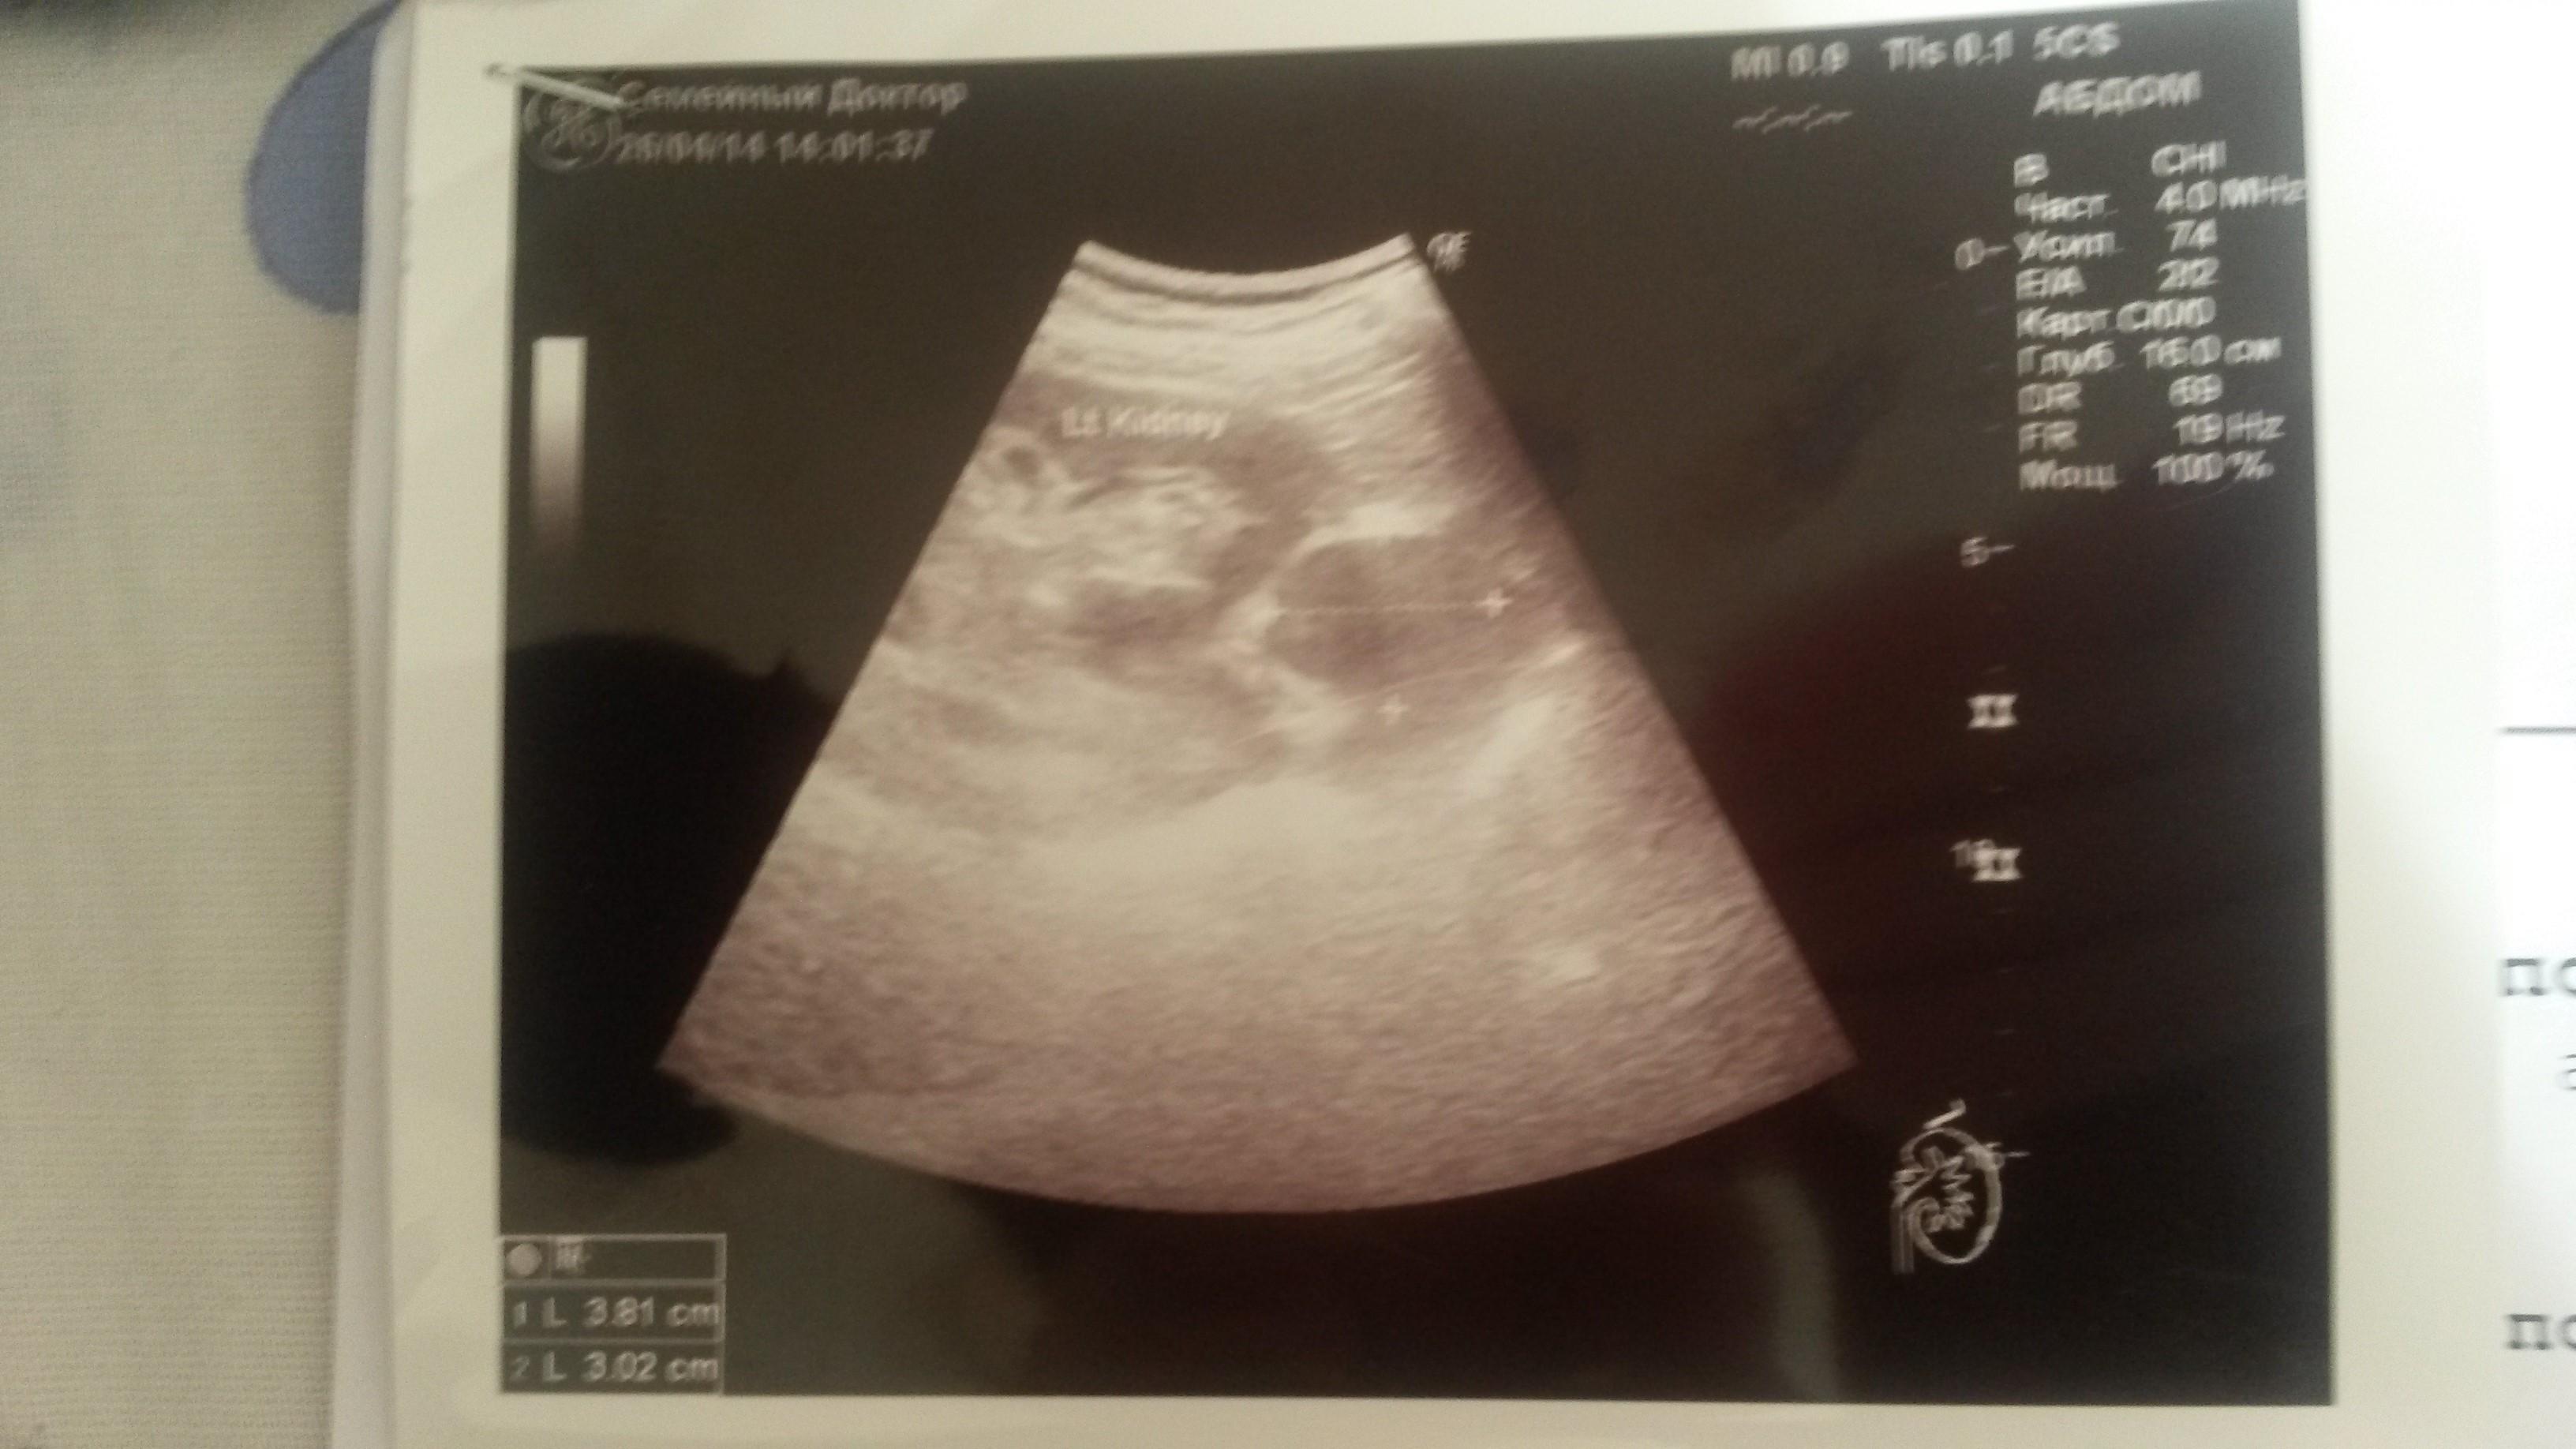

Здравствуйте, Мне 64 года на УЗИ брюшной полости в проекции левого надпочечника обнаружено гипоэхогенное образование 38 на 30 мм с четкими ровными контурами, однородной структуры. При ЦДК слабый смешанный кровоток. Размеры левой почки 120 на 58, контуры четкие, ровные, эхоструктура паренхимы однородная- 17 мм, ЧЛС центрально расположена. Сделали КТ...результаты Надпочечники расположены обычно. Отмечается утолщение тела и медиальной ножки левого надпочечника до 5 мм. В области надпочечником патологических образований не визуализируется. В заключении признаки гиперплазии левого надпочечника. На УЗИ есть объемное образование, а на КТ получается нет? Или может мы не правильно поняли результаты? Заранее спасибо.